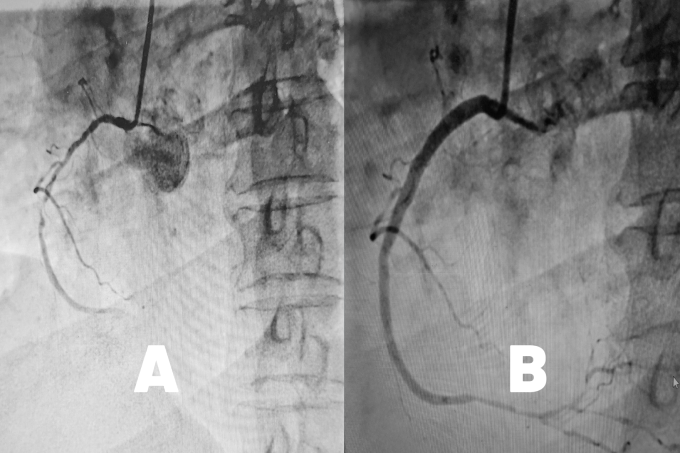

| Động mạch vành phải hẹp nặng (hình A) và sau khi được nong mạch đặt stent (hình B). Ảnh BVCC |